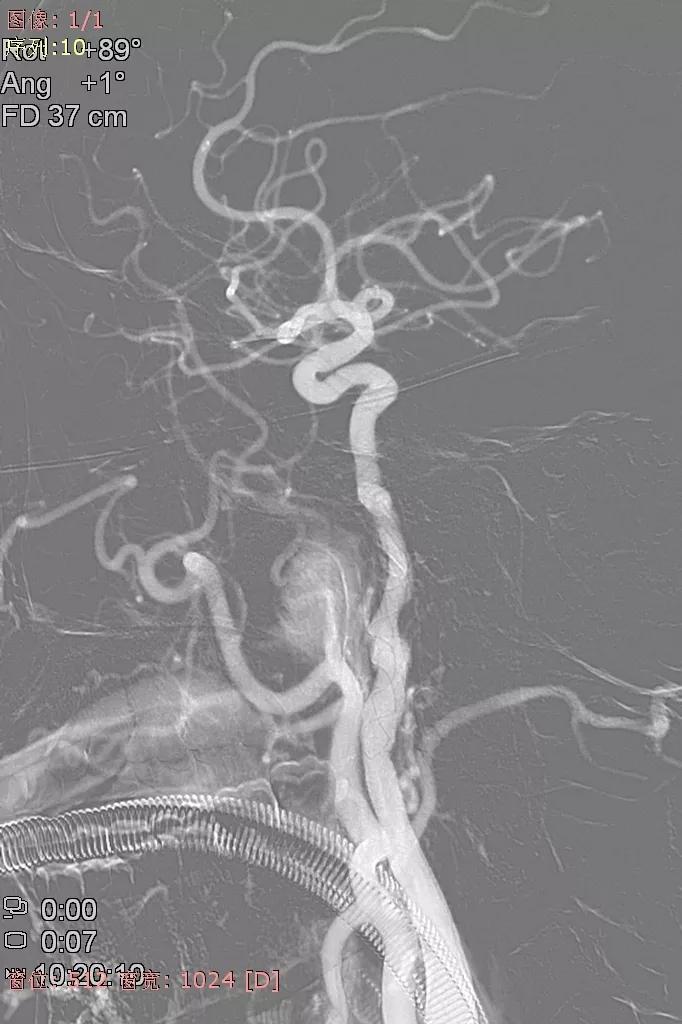

男,62y,因“突发头痛伴恶心呕吐1天”来院。

患者于入院前1天无明显诱因突发头。外院头颅CTA示:颅内动脉瘤。我院行DSA示:左侧大脑中动脉动脉瘤。

全脑血管造影可见左侧大脑中动脉动脉瘤,瘤体最大径:16.7mm,瘤颈宽:8.3mm。

Synchro 14微导丝导引支架导管,远端送入左侧中动脉下干远端困难,支架导管内穿行Tracxseed微导丝,双导丝导引支架导管顺利进入左侧中动脉下干远端,尾部链接Y阀1个,压力带1个。

经支架导管,置入Tubridge® 3.0×30mm,释放位置良好。

复查造影,动脉瘤造影剂明显滞留,各血管及分支通畅,流速正常。手术结束。